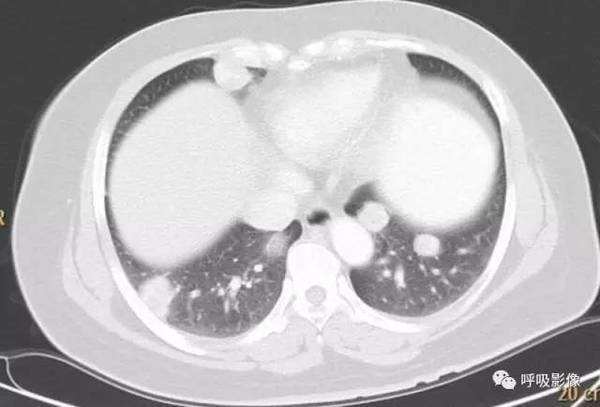

绒毛膜癌较侵袭性葡萄胎易发生转移。侵袭性葡萄胎肺部转移多以结节为主(图1),而绒毛膜癌肺部转移种类较多。

图1 女,31岁,侵袭性葡萄胎